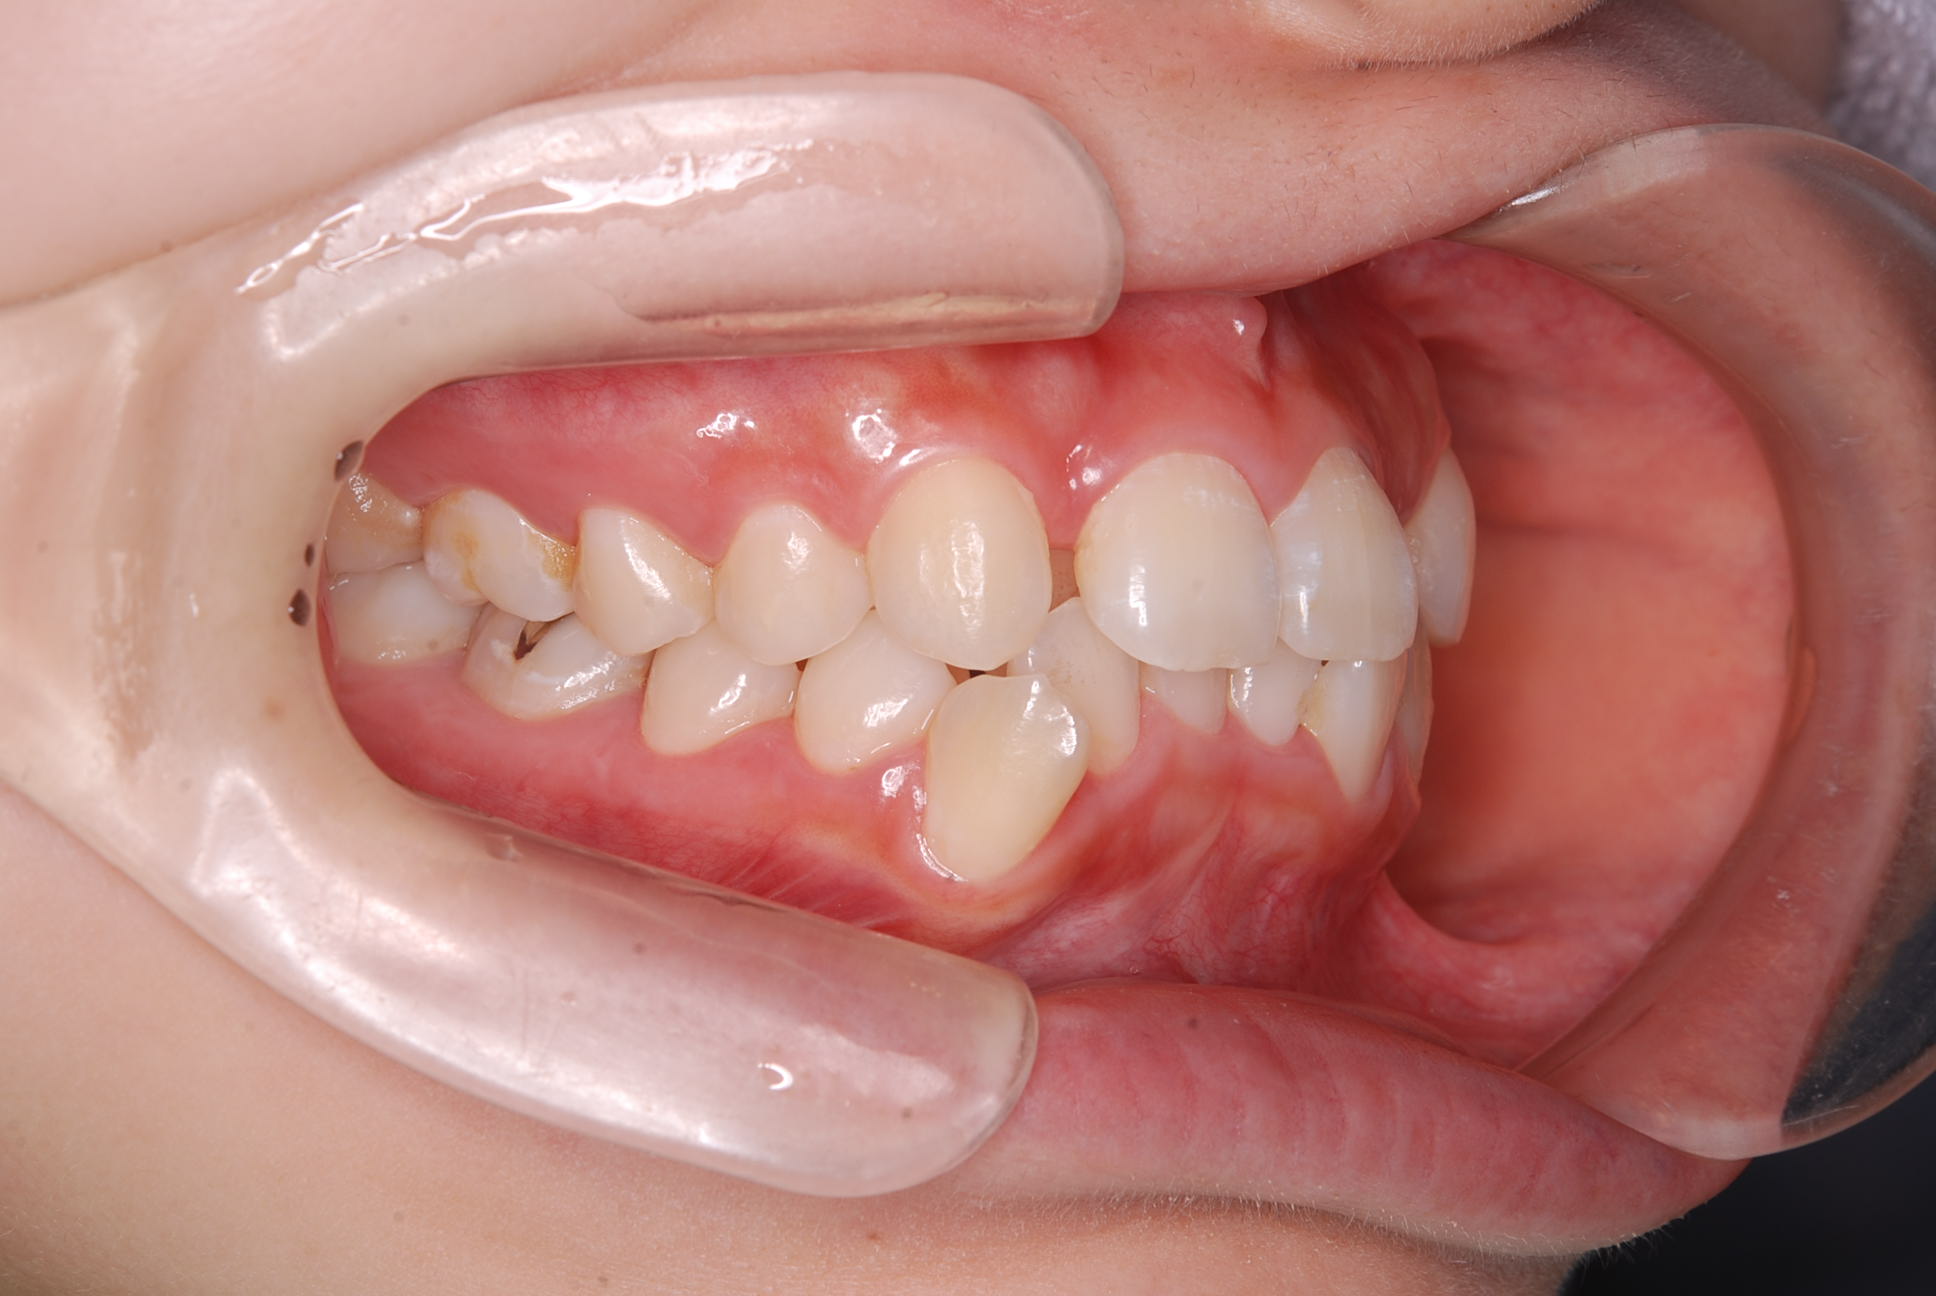

歯並びのガタガタ

上下顎に叢生(歯並びのガタガタ) と部分的な反対咬合を認める。